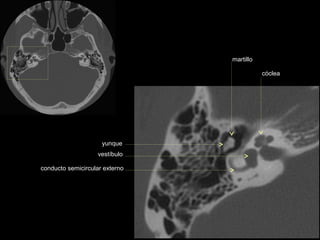

CATEDRA DE RADIOLOGIA U.N.L.P.   Hueso temporal normal              Edición 2002

seno maxilar

conducto

carotídeo

auditivo externo

protuberancia

occipital externa

trompa de Eustaquio

conducto auditivo externo

celdillas mastoideas

eminencia piramidal

seno timpánico

receso del n. facial

nervio facial (3era)

estribo (cruras)

nervio facial

ventana oval

martillo

yunque

cóclea

vestíbulo

conducto semicircular externo

articulación yunque/martillo

conducto auditivo interno

conducto semicircular posterior

antro mastoideo

celdillas retrolaberínticas

conducto semicircular

superior

conducto semicircular superior

cabeza del martillo

procidencia de meninges

tendón tensor del tímpano

conducto carotídeo

espina supra y retrotimpánica

nervio facial (2da)

nervio facial (1era)

cresta falciforme

promontorio

estribo

membrana

timpánica

externo

ventana redonda